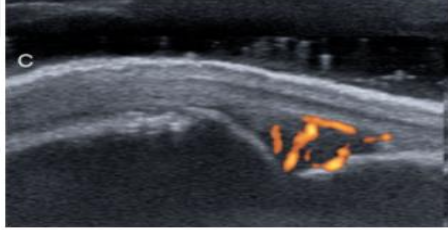

Grade this doppler

Grade 3: >50% of the synovial hypertrophy is covered by signals